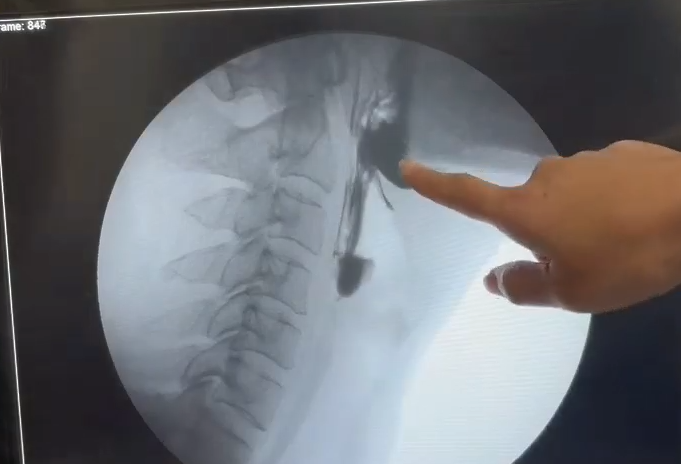

患者因延髓梗死入院,入院时存在严重吞咽障碍,无法经口进食,需依赖鼻饲管维持营养。入院后行吞咽造影检查(VFSS),结果显示:

· 环咽肌不开放,导致食物堆积在咽喉部,无法进入食管。

· 进食安全性差,存在误吸风险。